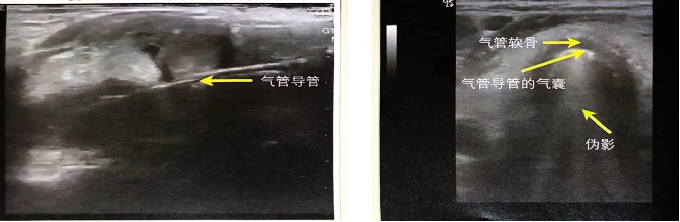

气道超声(图17)常用于气管插管术或气管切开术。对于气管切开术操作前可用超声扫描:鉴别气管、气管旁组织及血管;明确气管的深度;选择最佳切口部位。在操作过程中也可以应用超声进行指导。对于气管插管术,插管后可以应用超声来确定气管导管在气管内、气囊充气情况(调整探头向尾端成角,可找到气囊)(图18)。操作时出现强回声,可以看到伪影,气囊打气和放气可观察到声影移动。

图片

图18  气管插管患者的气道超声